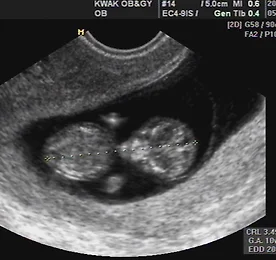

네 번째 검진, GA 12w+4 지난 목요일에 색시와 함께 검진을 받으러 다녀왔다. 색시도 오랜만에 회사에 휴가내고, 여유있게 쉬다가 오후에 집에서 나서서 병원에 갔다. 평일이었지만 적지 않은 산모들이 있었다. 이번에는 약 12주 정도 되는 때라 목덜미 투명대, Nuchal Translucency 측정도 같이 했다. 다행히 우리 한라는 0.17cm로 측정되어 별다른 문제는 없는 것으로 나왔다. 사실, 완벽한 정중면에서 측정한 것이 아니라 부정확할 수도 있겠지만, 정중면에서 잰 것이 가장 좁게 나오게 될터라, 넓게 측정될 非정중면에서의 측정값이 기준값보다 낮으니 안심해도 괜찮을 것이다. 게다가, 정중면 측정으로 했으면 비싼 정밀초음파 비용을 내야 했지만, 非정중면이어서 일반 초음파 비용만 냈다. :) 우리 한라가 엄마 뱃 속에서부터 효도.. 더보기